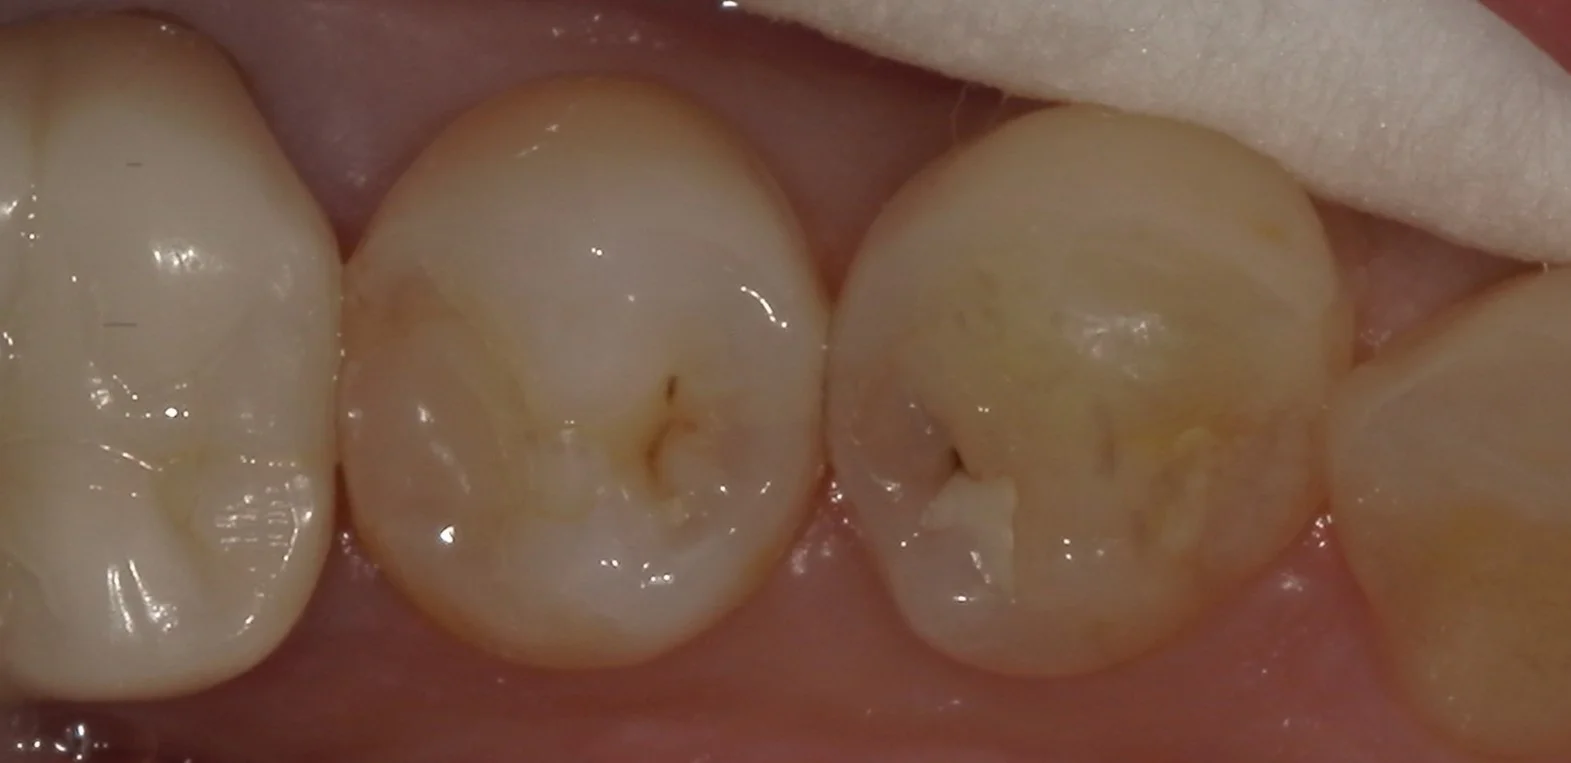

では術前の写真からです。

中央にある2本を治療したのですが、どこが虫歯か分かりますかね?